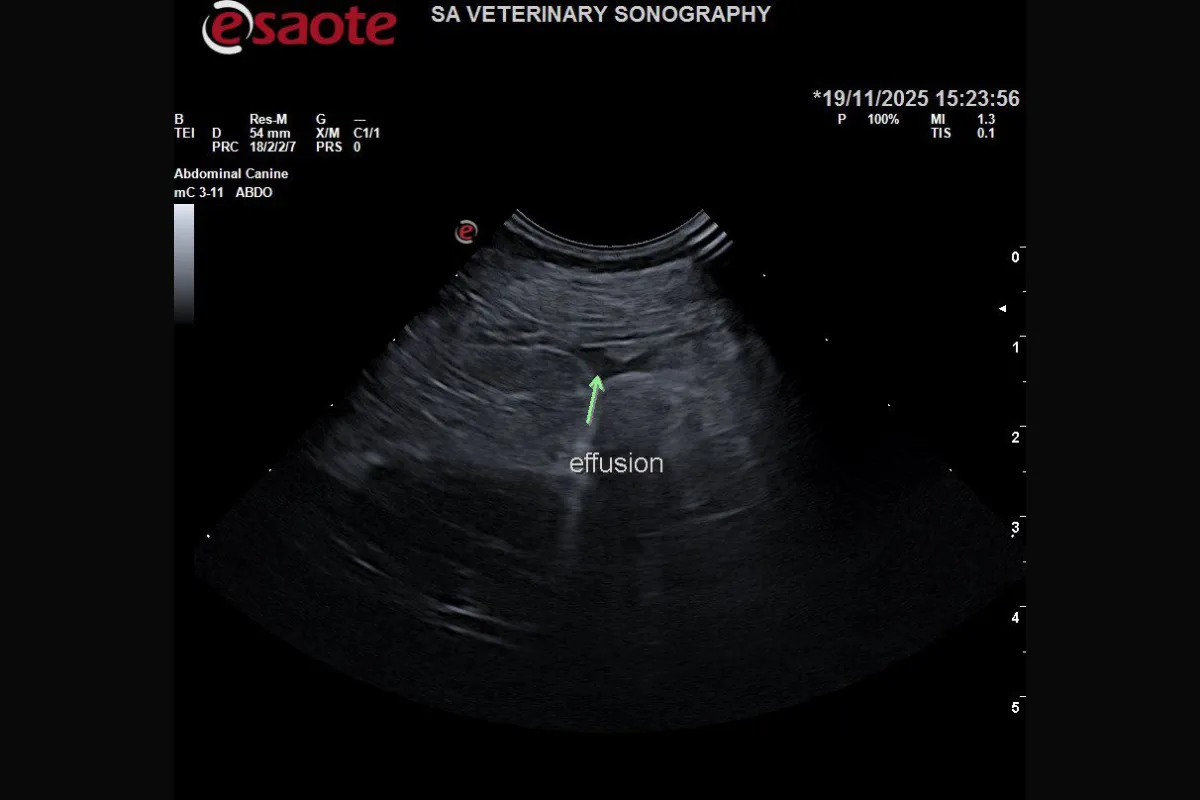

Ultrasound revealed extensive inflammation in the cranial abdomen, with hyperechoic, hazy fat and reduced acoustic detail. A small volume of echogenic effusion surrounded the area.

A sample of the abdominal effusion collected via abdominocentesis confirmed septic peritonitis, without evidence of bile. Combining peritonitis, emphysematous changes, and a suspected liver abscess, emergency surgery became the clear next step.